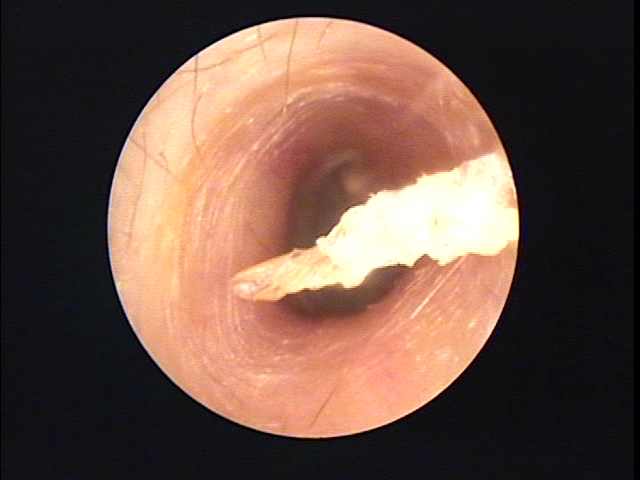

耳について | 千葉耳鼻咽喉科クリニック from chibacl.com